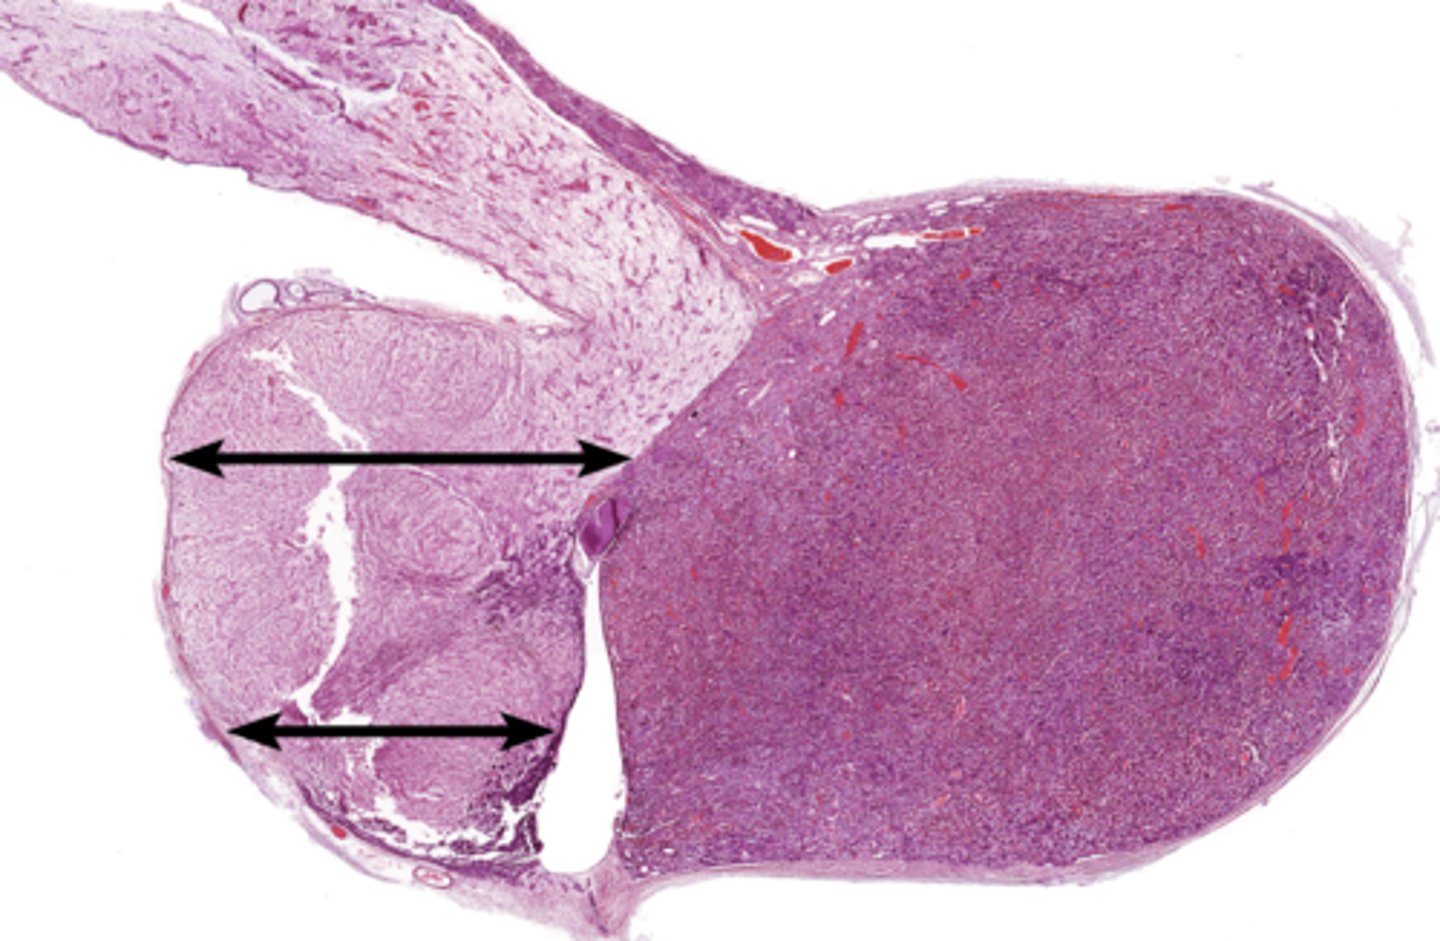

Parathyroid gland

Oxyphil cell

Principal cell